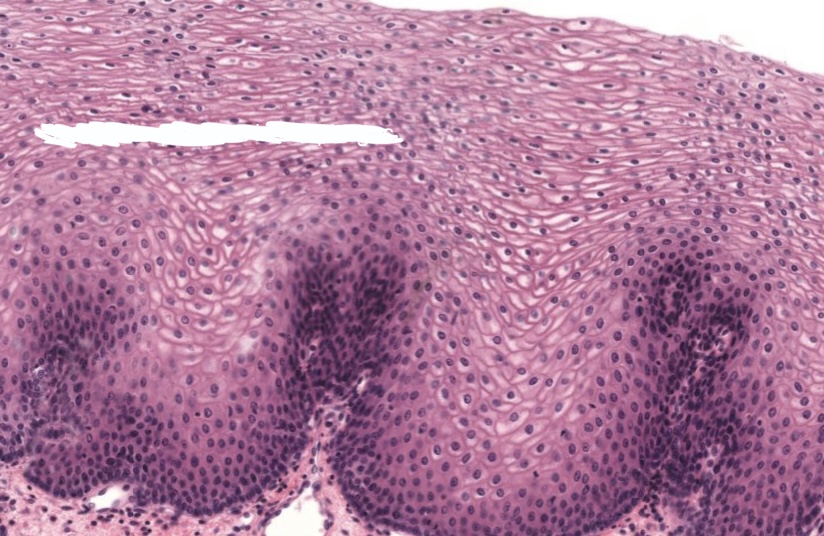

term image

Strat squamous in esophagus. Top cells are flat, living cells not keratinized